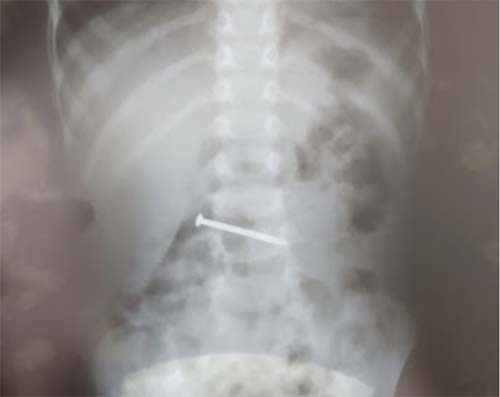

Um criança de apenas dois anos engoliu um prego e deixou seus familiares assustados, nessa quarta-feira (9), na cidade de Inhapi, no Alto Sertão de Alagoas.

O menor deu entrada no Hospital Regional Clodolfo Rodrigues, em Santana do Ipanema, com sintomas de engasgos. De início, os familiares informaram que não sabiam do que se tratava, mas disseram tinham visto um objeto prata na boca da criança e que não conseguiram tirar a tempo.

Na unidade de saúde, a equipe médica submeteu a criança a exames de radiografia. O resultado apontou a presença de um prego dentro da barriga da criança.

Os pais foram orientados a observar, até que o objeto seja expelido pelo corpo por meio das fezes. Caso contrário, a criança deverá ser submetida a um procedimento cirúrgico para a retirada do prego.